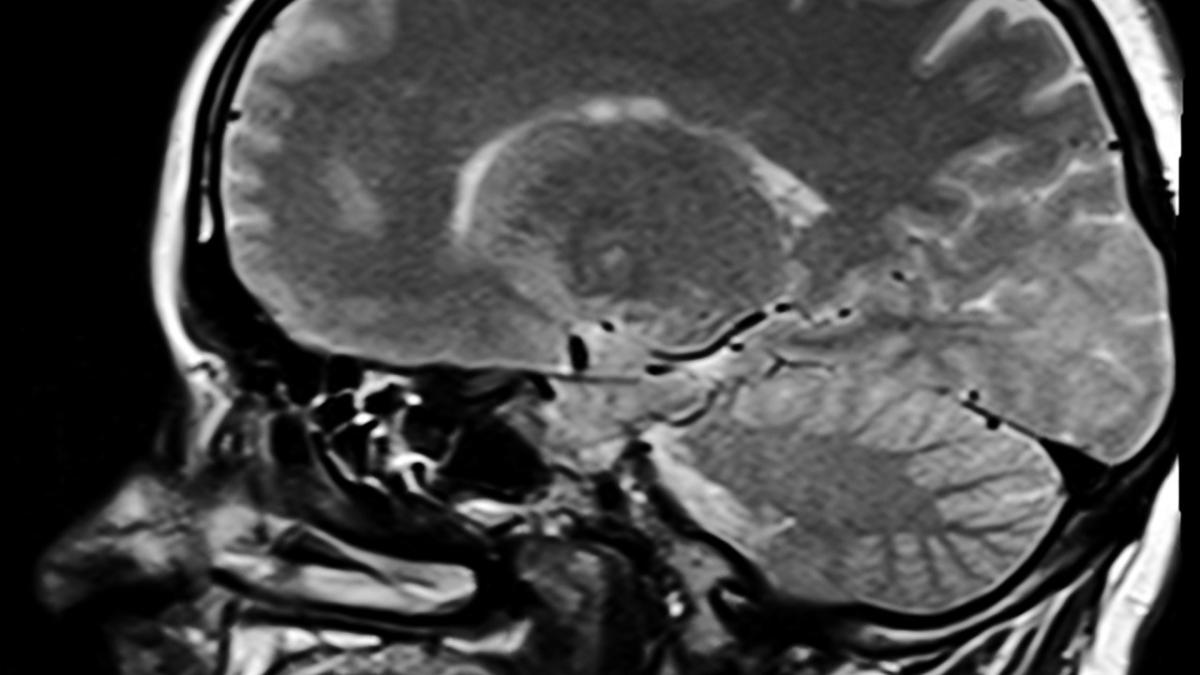

afectiune-neurologica-rara-legata-de-infectarea-cu-sars-cov-2-n-21-de-tari_01049500 Studiu: Afecțiune neurologică rară, legată de infectarea cu SARS-CoV-2 în 21 de țări / Foto cu caracter ilustrativ: Pixabay

O afecțiune neurologică rară a fost legată de infectarea cu SARS-CoV-2 în 21 de țări.

Cercetătorii continuă să investigheze efectele complete ale acestei infectării cu SARS-CoV-2, inclusiv cele neobișnuite, iar o nouă analiză a legat acum infecția de o afecțiune neurologică rară.

Mielita transversă acută (ATM) - o inflamație a măduvei spinării care poate provoca durere, paralizie și probleme senzoriale - a fost identificată în 43 de cazuri de adulți infectați cu SARS-CoV-2 din 21 de țări, cu vârste cuprinse între 21 și 73 de ani, precum și 3 copii cu vârsta cuprinsă între 3 - 14 ani. Revizuirea colectează împreună cercetări anterioare și rapoarte de caz și, potrivit echipei din spatele acesteia, datele sunt suficiente pentru a justifica o investigație ulterioară. Într-un anumit an, incidența ATM-ului este estimată la doar 1,34-4,6 cazuri la un milion de persoane.